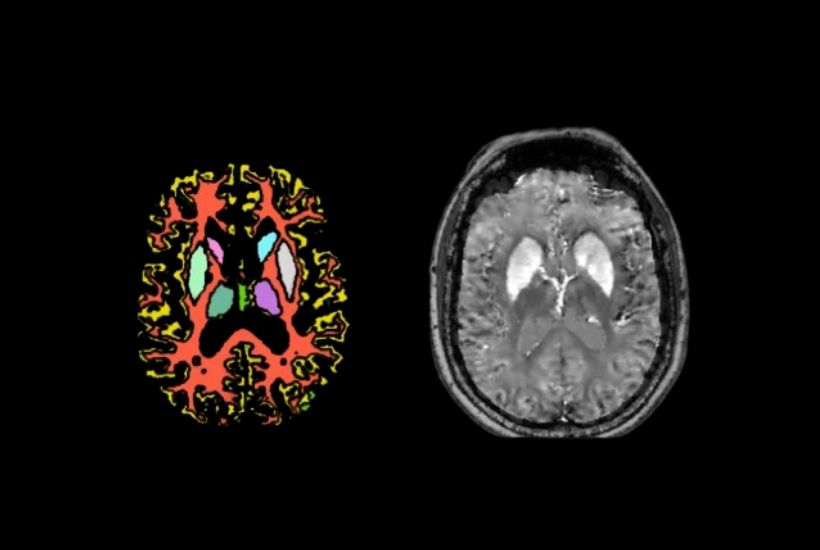

CEA NEUROSPIN x GHU SAINTE-ANNE

QSM4 ALZHEIMER DISEASE

Objectives

Earlier diagnosis, better patient stratification:

- Compare brain images of patients with brain images of normal cognitive ageing

- Establish correlations between iron imaging and the clinical manifestations of the disease

- Characterise atypical profiles of Alzheimer’s disease using information provided by iron imaging.